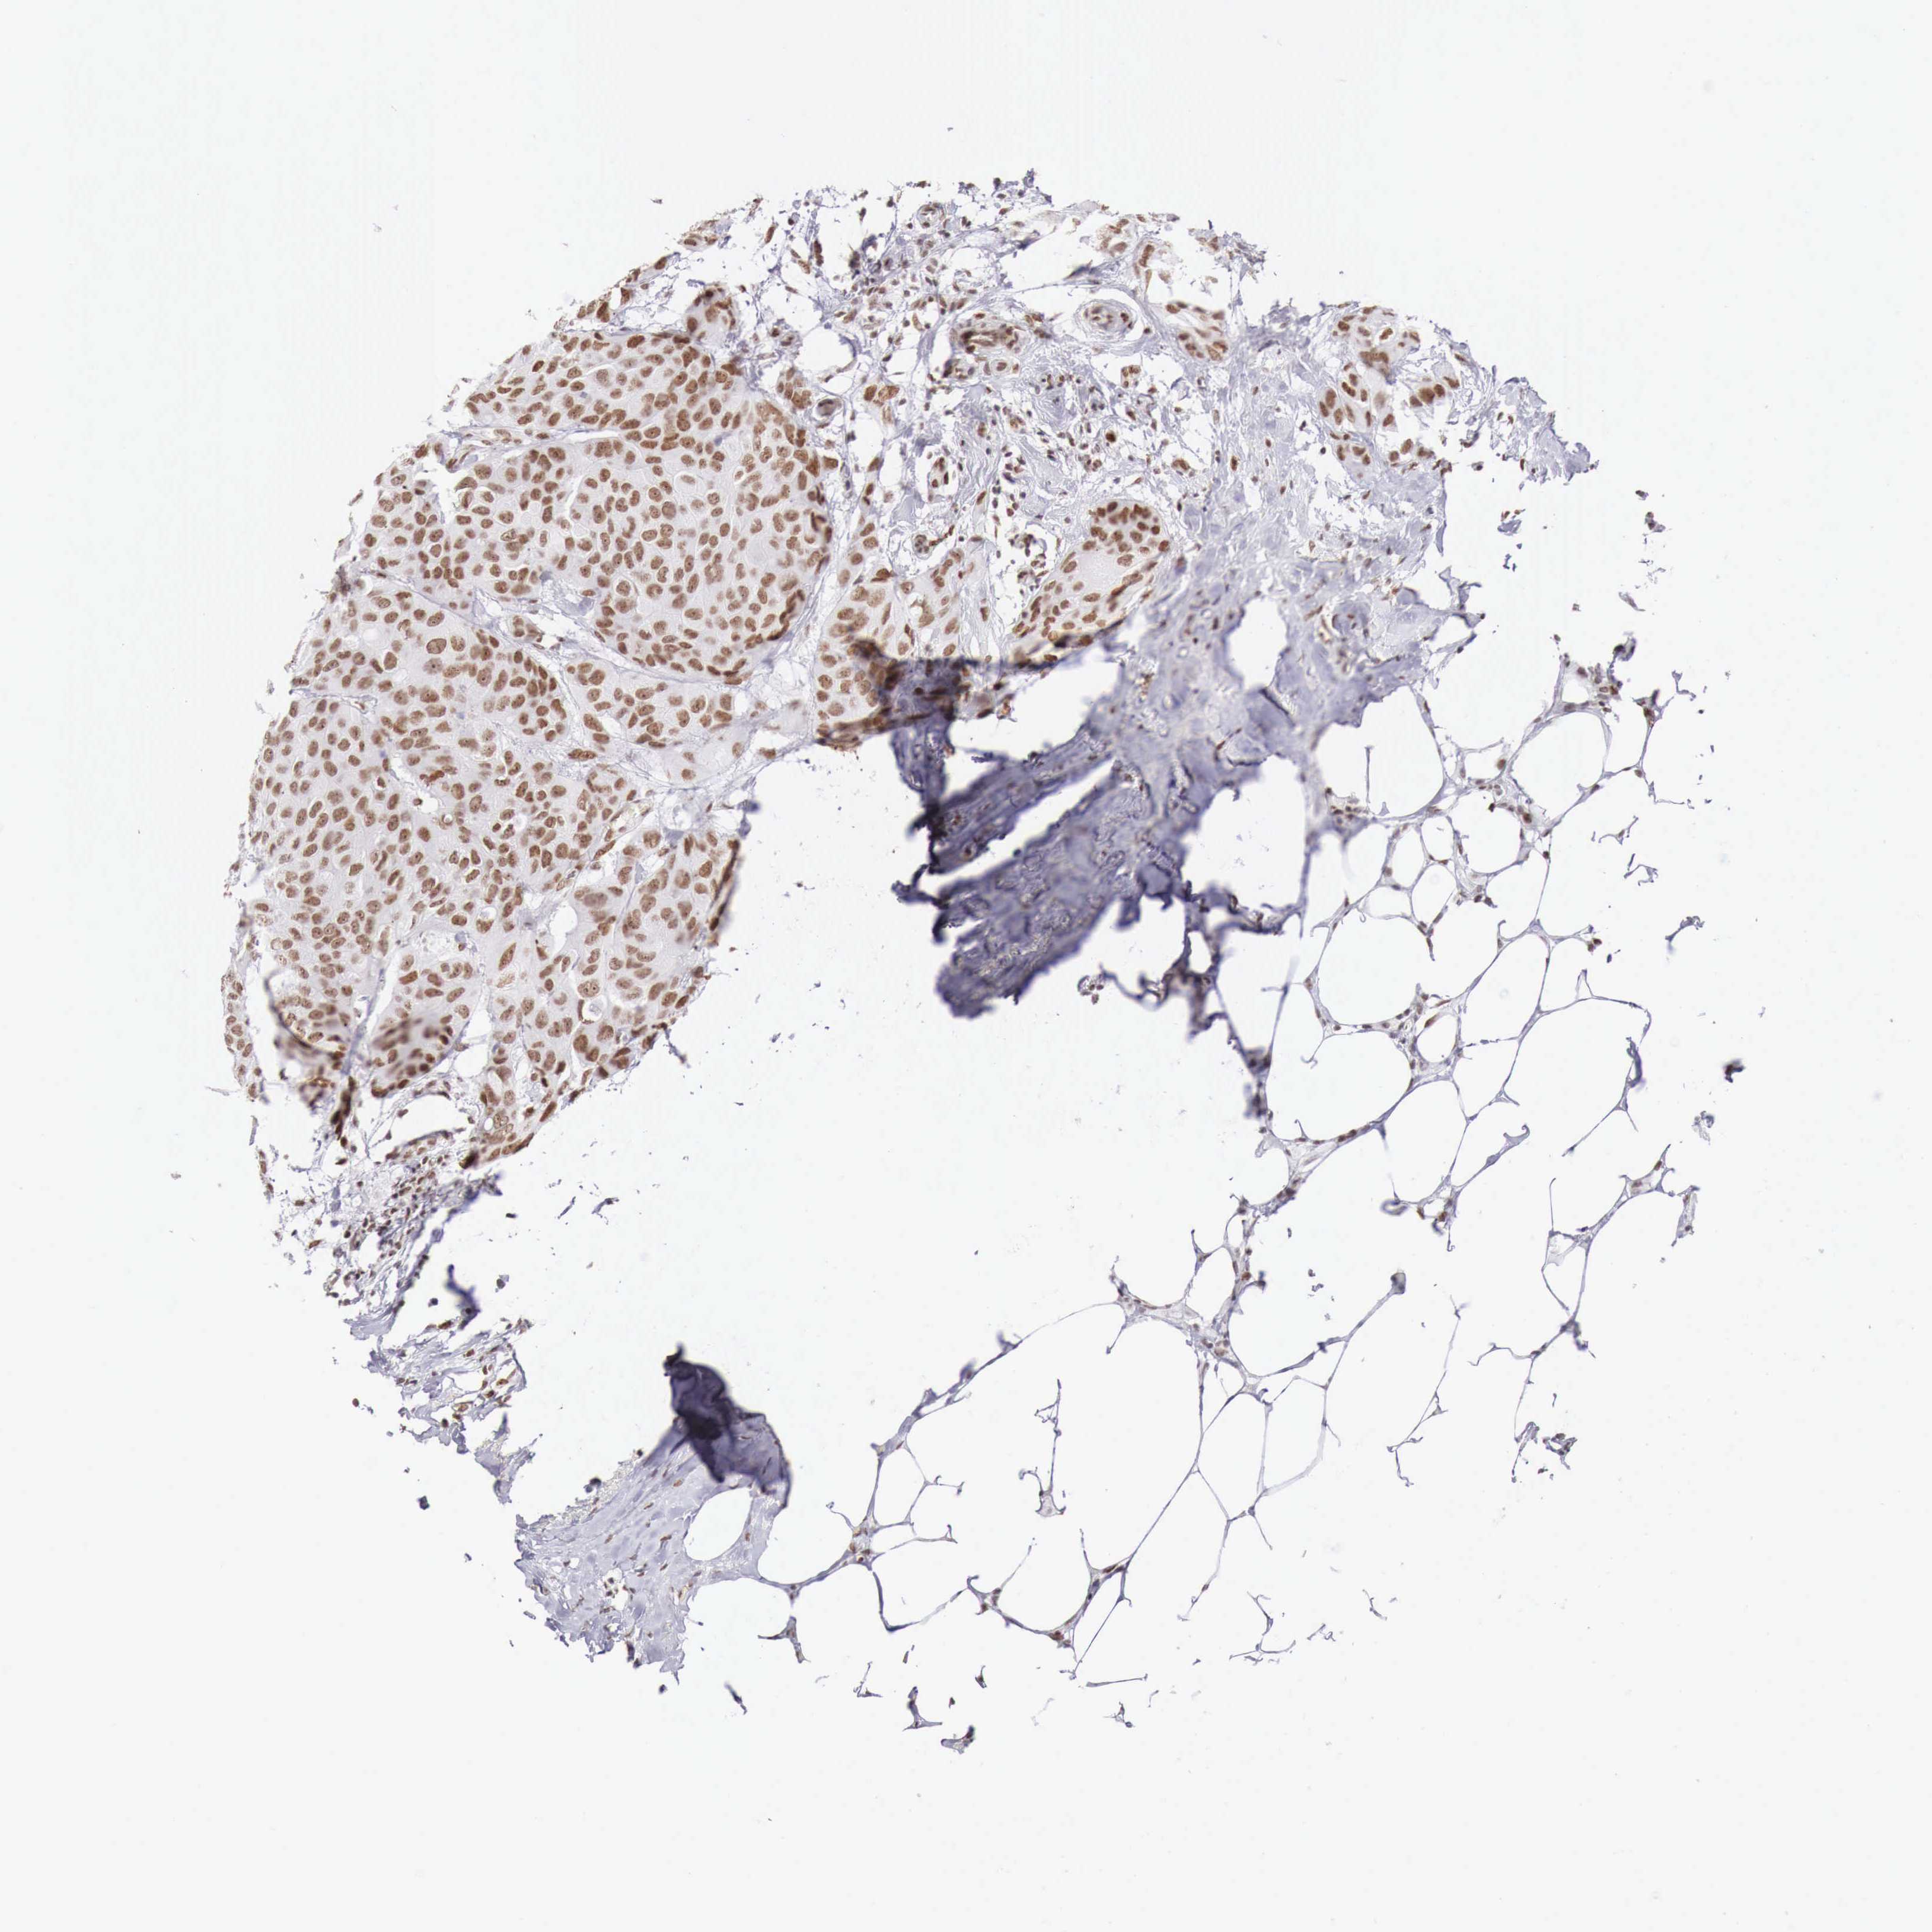

BRCA TCGA BRCA VALIDATION PROTEIN EXPRESSION

ANTIBODIES

AND

VALIDATION